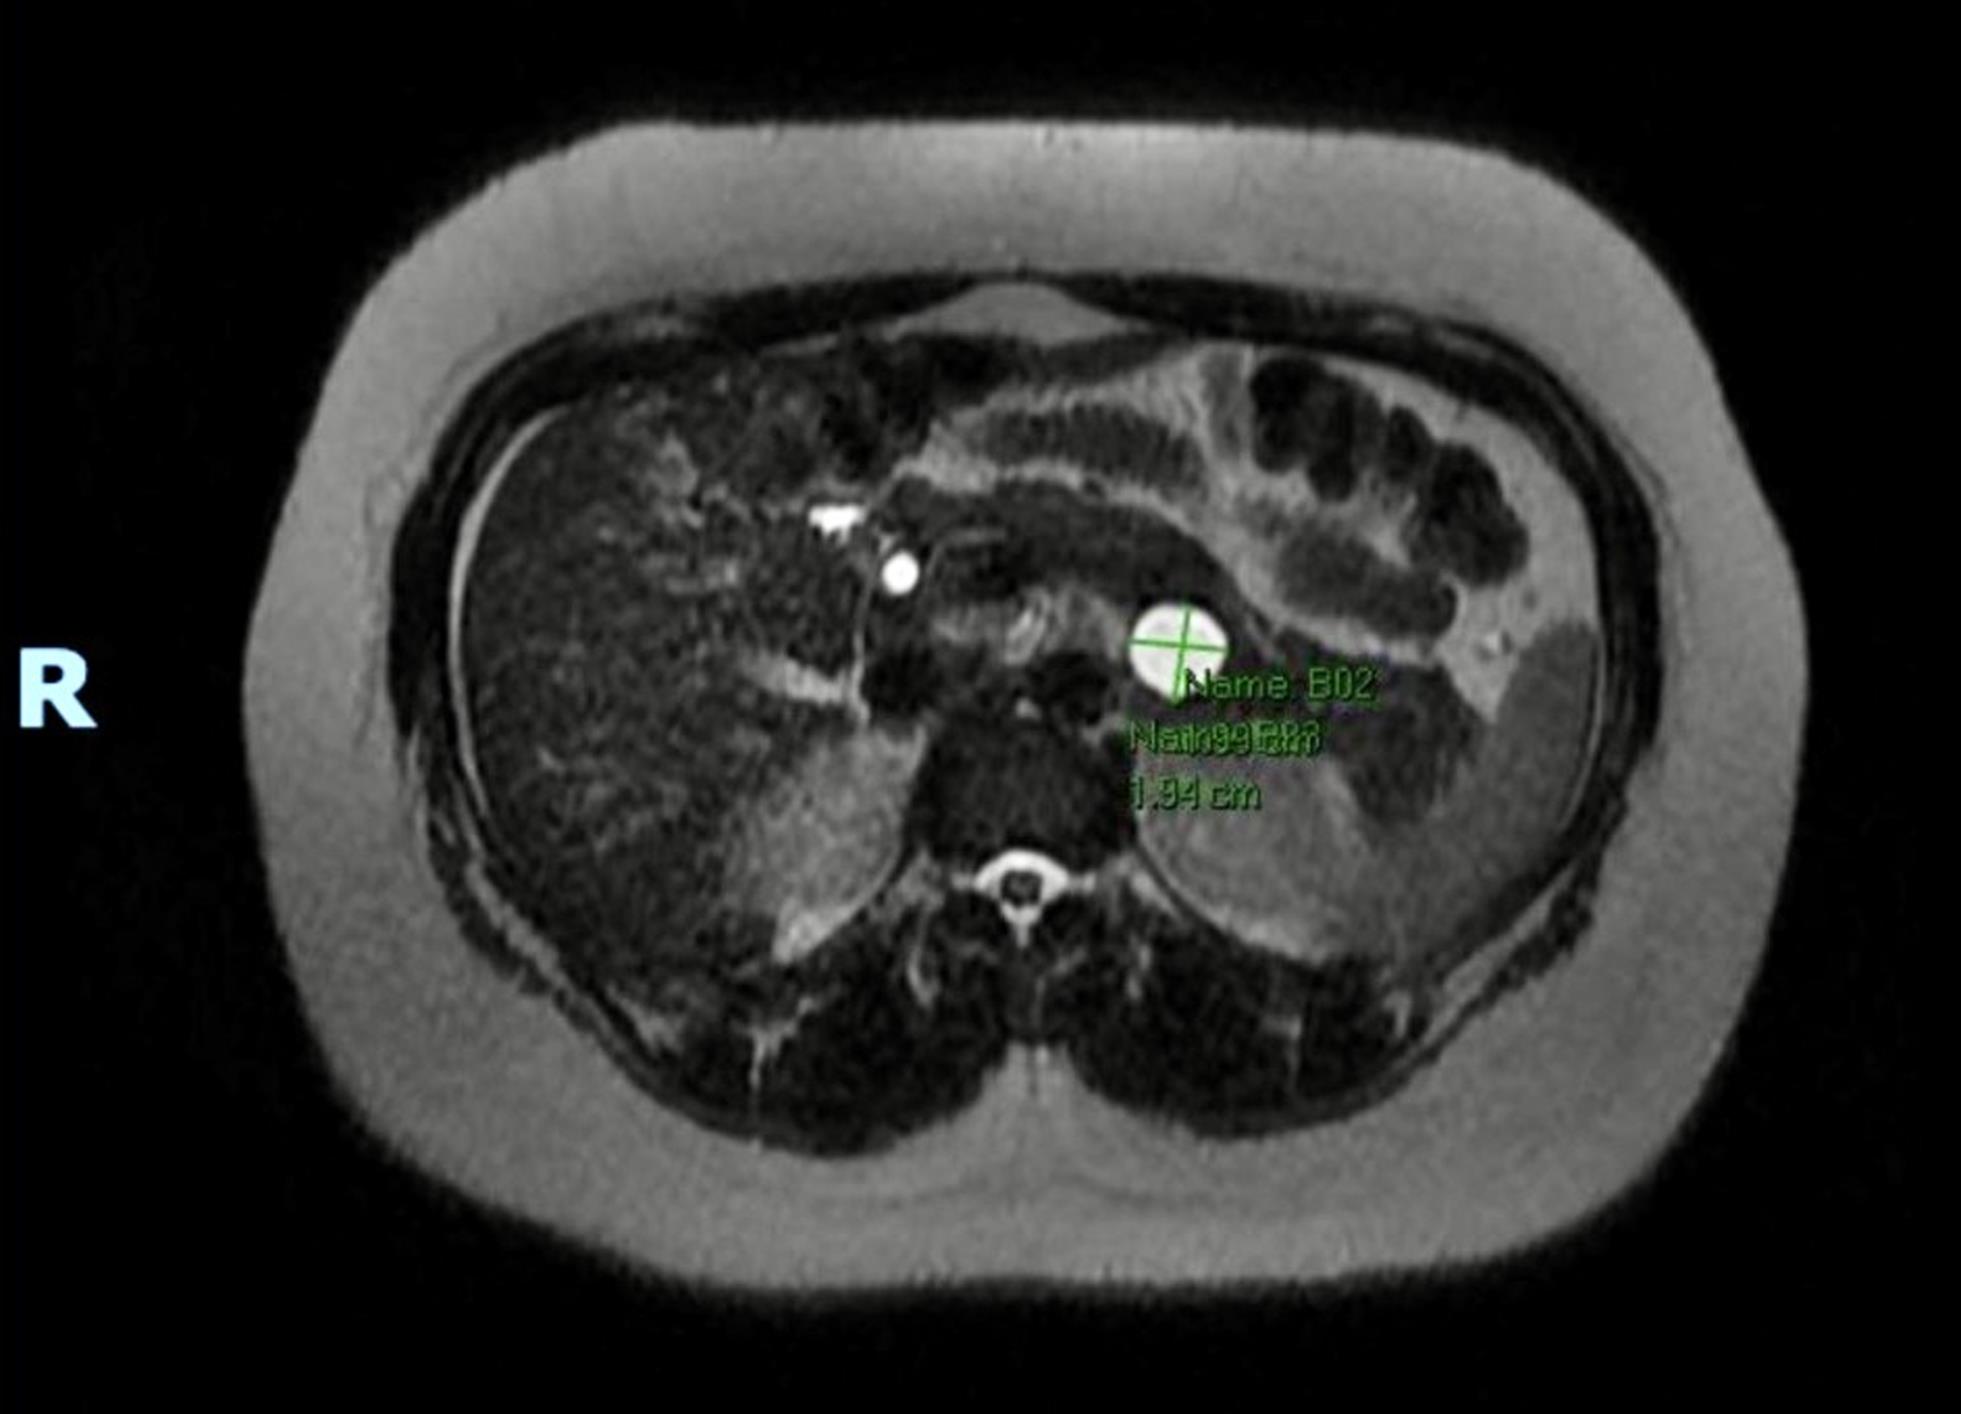

Yun Bian, Jing Li, Zhaoshen Li, Jianping Lu, Chengwei Shao, Shiyuan Liu, Min Chen, Xun Li, on behalf of the Professional Committee of Pancreatic Diseases, Chinese Medical Doctor Association; the Radiology Branch of the Chinese Medical Association; the National Clinical Research Center for Digestive Diseases (Shanghai); and the Shanghai Medical Association Radiology Quality Control Center

Pancreatic solid tumors encompass diverse pathological subtypes. Objective, accurate, and comprehensive imaging examinations and diagnostic reports are essential for preoperative staging, treatment planning, and prognostic evaluation. Currently, China lacks corresponding guidelines or consensus documents, leading to prominent issues including subjective diagnostic reports, incomplete descriptions, and inconsistent terminology. The present guideline was developed to standardize diagnostic imaging reporting of pancreatic solid tumors in China. Relevant domestic and international evidence on imaging examination techniques, key reporting elements, and diagnostic criteria was systematically reviewed and synthesized. This guideline was developed by a multidisciplinary expert panel through systematic evidence retrieval and appraisal, GRADE-based recommendation grading, modified Delphi consensus, and external review. A total of 20 evidence-based recommendations, 13 strong and 7 weak, were formulated, in aspects of imaging examination and diagnostic reporting standards, including the measurement of the tumor size of pancreatic solid tumors, assessment of the obstruction of the main pancreatic duct and common bile duct, definition, assessment, and clinical significance of pancreatic parenchymal atrophy, the assessment of obstructive acute pancreatitis, pseudocysts/retention cysts, and peripancreatic vessels, criteria for resectability, regional lymph node assessment, criteria for suspicious lymph nodes and descriptions of their specific location, and detection of hepatic and peritoneal metastases. Implementation of this guideline in clinical practice will help standardize the accuracy and consistency of diagnostic imaging reports for pancreatic solid tumors in China, thereby advancing standardized imaging diagnosis and informing clinical treatment decisions.